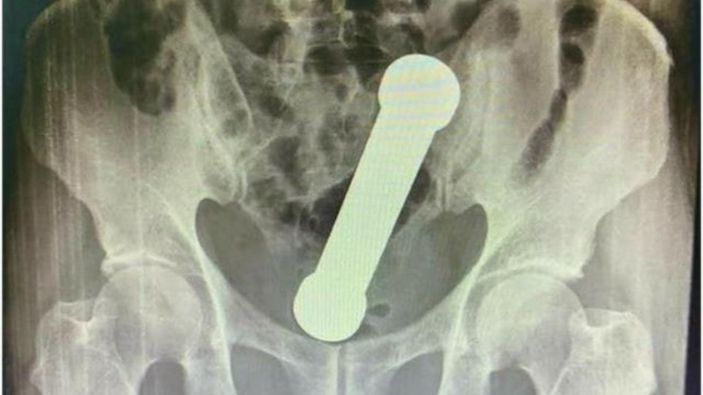

Karın ağrısı şikayetiyle hastaneye giden 54 yaşındaki adamın makatından 2 kiloluk dambıl çıkarıldı.

Hastaneye karın ağrısı şikayetiyle başvurarak doktorlara nedenini söylemeyen hasta, röntgen sonucunda içerideki dambılı gördü.